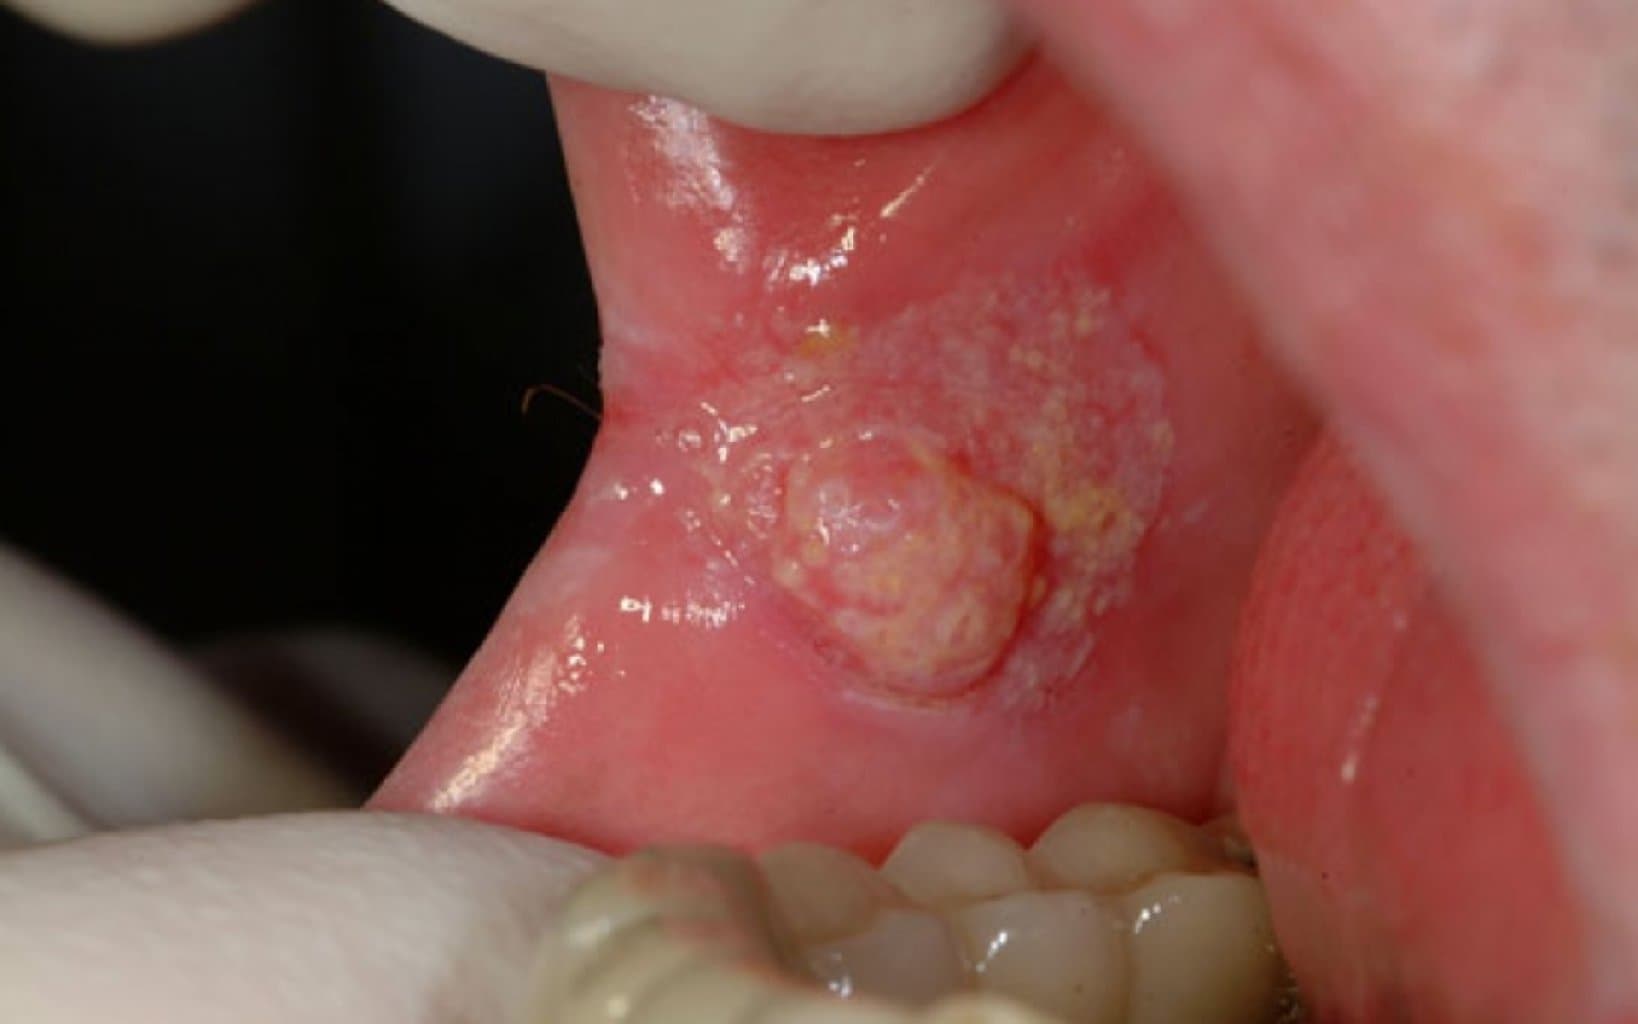

- Ağızda və ya Dodaqlarda Yaralar: Uzun müddət sağalmayan və qanaxan yaralar.

- Dil və ya Yanakların İçində Qalınlaşmalar: Ağız boşluğunda hiss edilən qalınlaşma və ya şişkinlik.